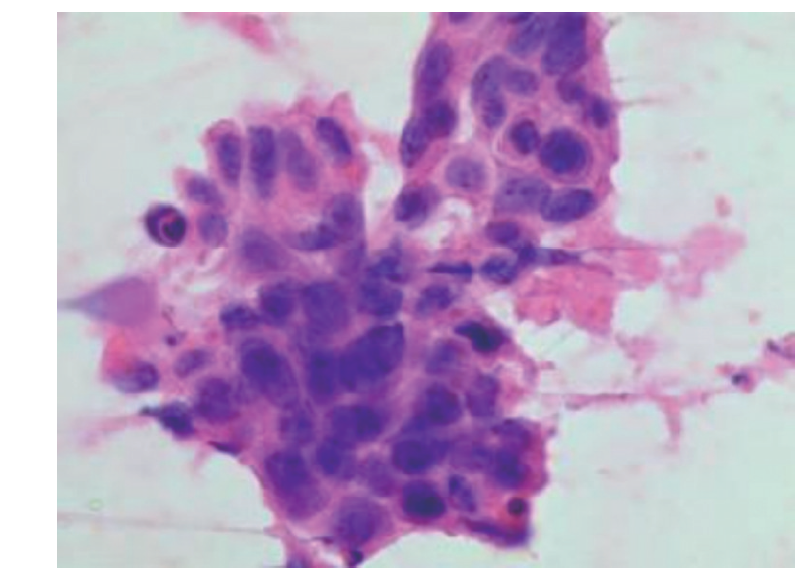

软腭及食管多原发鳞状细胞癌鼻尖皮肤转移1例

多原发鳞状细胞癌发生鼻尖皮肤转移极为罕见,文献报道较少,且鳞状细胞癌病理表现相似,较难诊断。现回顾性分析1例软腭及食管多发鳞状细胞癌出现远处鼻尖皮肤转移患者的临床资料,结合相关文献复习,以提高对本类疾病的认识。